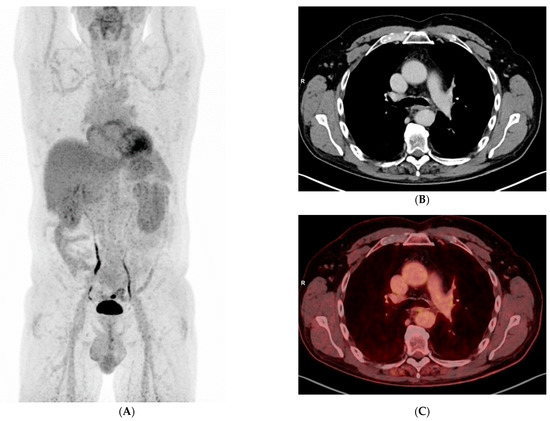

3. Results